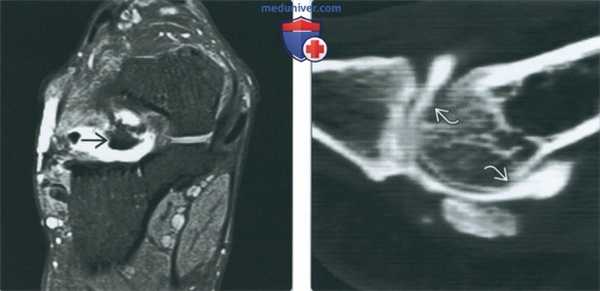

(Слева) МР-артрография в режиме Т1ВИ FS, коронарный срез: в пазухе предплюсны визуализируется крупный костный фрагмент, окруженный контрастным препаратом. Картина обусловлена несрастающимся костно-хрящевым переломом латерального отростка со смещением.

(Справа) КТ-артрография, сагиттальный срез: отмечается истончение хряща головки первой плюсневой кости в нескольких местах, что свидетельствует в пользу остеоартроза, а не травмы.